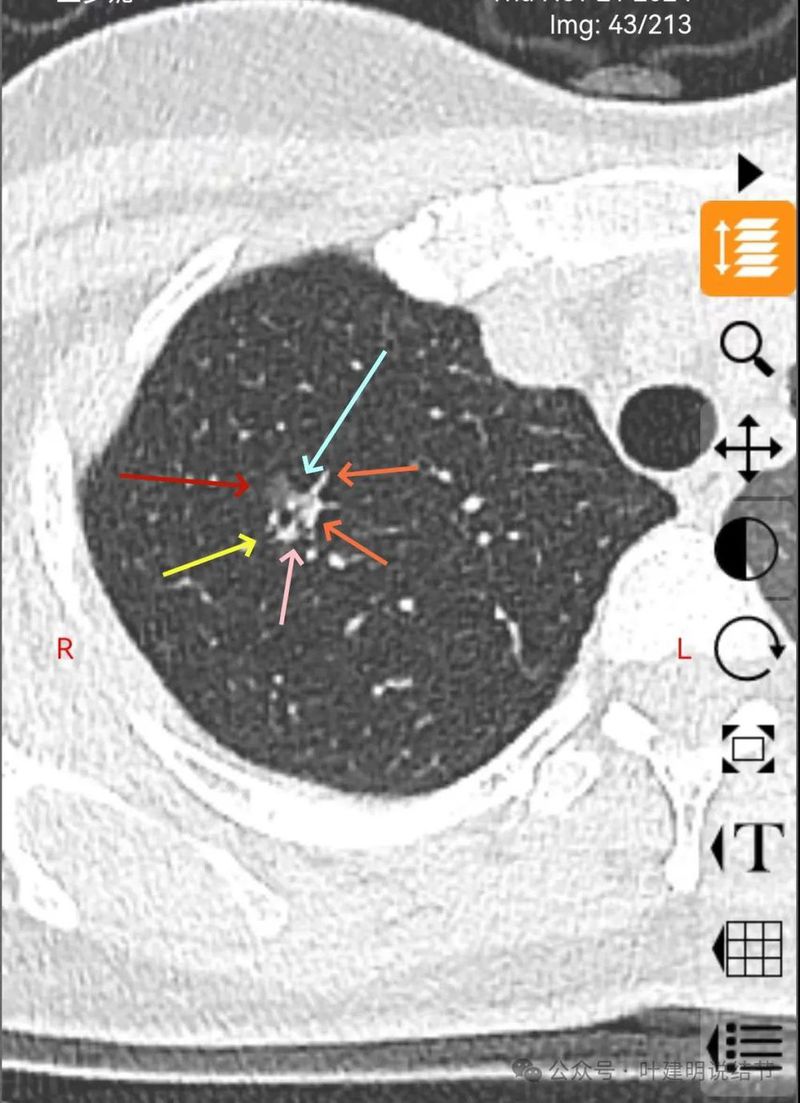

右上叶磨玻璃结节,轮廓较清,密度较淡,有小血管进入。

表面不平,分叶明显,灶边有小空泡征,灶边另有多处血管贴边,也见血管分支进入。

混合密度,月牙铲征,轮廓清,血管多支进入,灶内实性成分明显,表面不平分叶,灶内细支气管扩张。